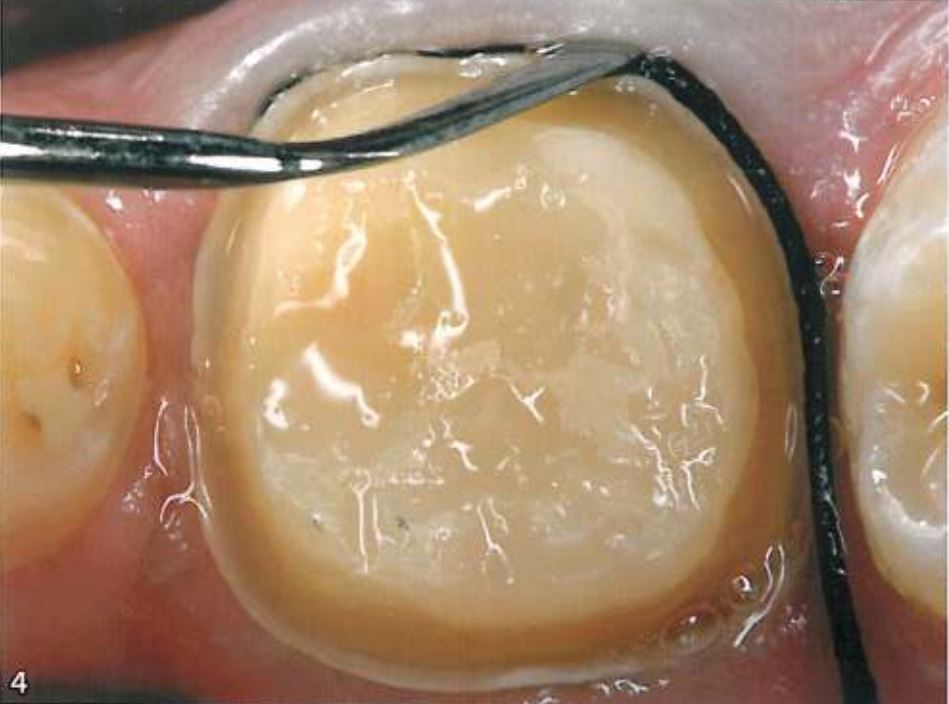

Khi sử dụng kĩ thuật đặt chỉ đôi (2 sợi), thì sợi chỉ với đường kính nhỏ hơn được đặt vào trước tiên. Sợi chỉ đầu tiên này nhằm giúp ngăn ngừa máu và dịch trào lên khi rút sợi chỉ thứ 2 ra (H3,4).

Chỉ co nướu phải được giữ nguyên trong khe nướu từ 5 – 10 phút để cho phép bề mặt chỉ hấp thụ bớt nước hay dịch nướu và tăng độ rộng khe hở giữa nướu với bề mặt răng.